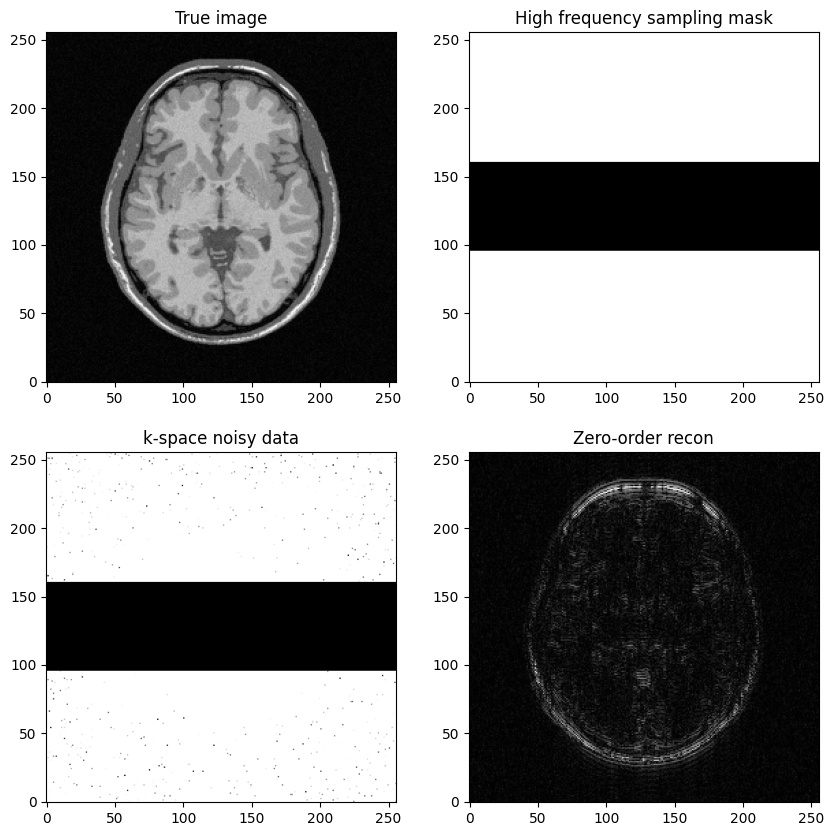

a high-frequency Cartesian mask is defined as the complementary set of the lines defined in to 1)

Next question: Construct a k-space sampling mask that consists of the high-frequency lines, just discard the central lines

Study the impact of the number of lines removed

fig, axs = plt.subplots(2, 2, figsize=(10, 10))

axs[0, 0].imshow(mri_img)

axs[0, 0].set_title("True image")

axs[0, 1].imshow(kspace_masklines)

axs[0, 1].set_title("High frequency sampling mask")

axs[1, 0].imshow(np.abs(kspace_data), vmax=0.01*np.abs(kspace_data).max())

axs[1, 0].set_title("k-space noisy data")

axs[1, 1].imshow(np.abs(image_rec0))

axs[1, 1].set_title("Zero-order recon")

plt.show()